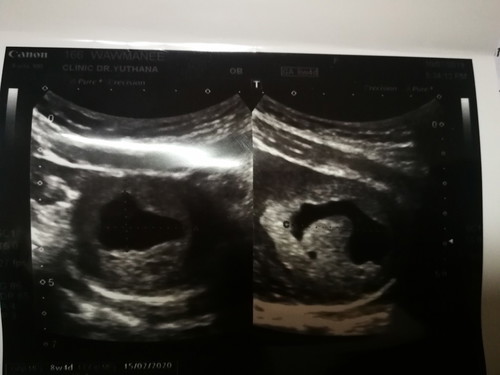

สู้ๆค่ะแม่ อย่าคิดมากค่ะ ท้องลมคือ ไม่มีตัวเด็กค่ะ ไม่ต้องเสียใจ เกิดจากการปฏิสนธิไม่สำเร็จค่ะ บ้านนี้เคยท้องลมเหมือนกันค่ะ ภาพนี้ตอน 8สัปดาห์ ไม่มีตัวเด็กเลยค่ะ หาไม่เจอ พอ10ส่ปดาห์ เลือดเริ่มออกมาทีละนิดๆ จน 12 สัปดาห์ไปตรวจอีกที ถุงครรภ์ฝ่อค่ะ

ภาพตอน 12 สัปดาห์ค่ะ หลังจากนั้นก็ยุติการตั้งครรภ์ ของเราแท้งสมบูรณ์ค่ะ ไม่ได้ขูด มันหลุดออกมาเองเลยค่ะ หลังจากที่หลุดไปประมาณ 6 เดือน น้องก็มาเลยค่ะ ตอนนี้ใกล้คลอดแล้วจ้า เป็นกำลังใจให้นะคะ 🥰🥰